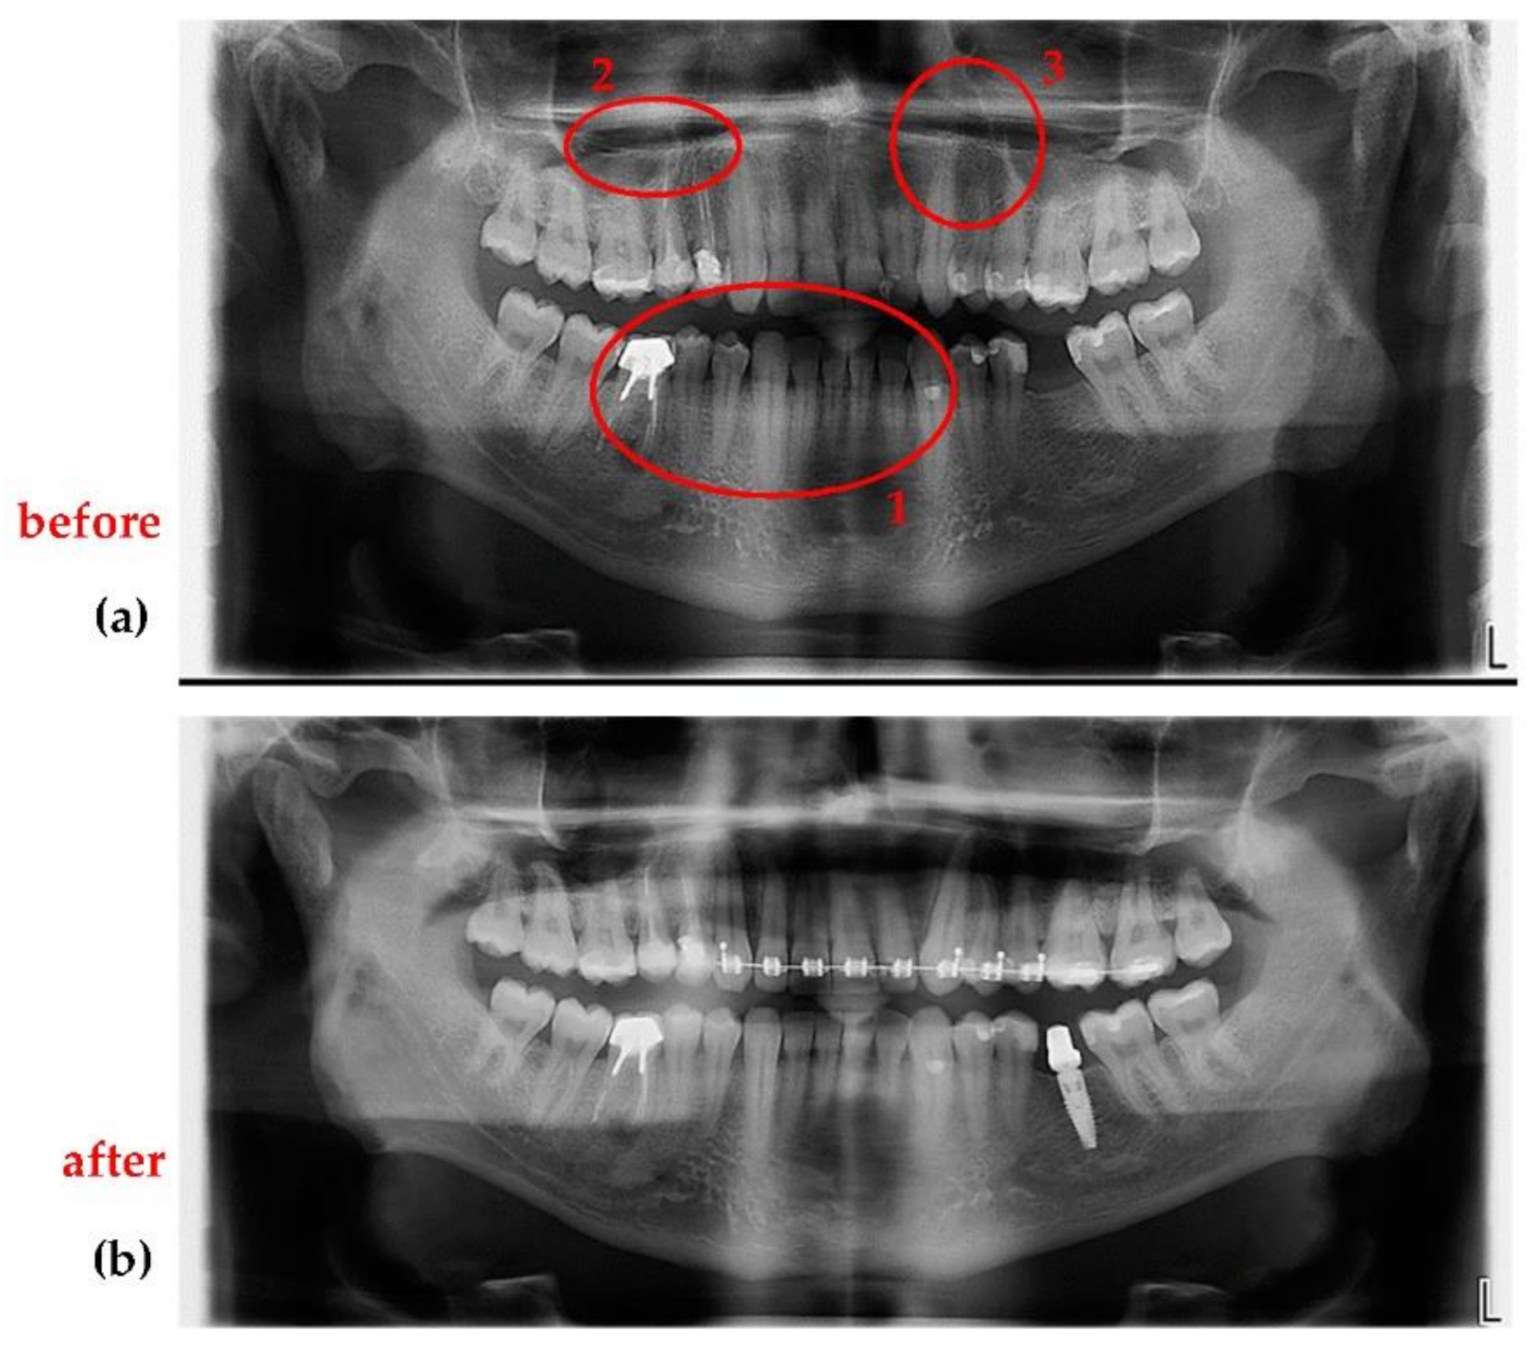

- Jewelry or any metal around the head or neck must be taken off, otherwise artifacts may appear on radiographs (Figure 17a). This is a general requirement, irrespective of the calibration procedure using OCT. On the other hand, implants and some materials used for dental crowns or dental fillings do not produce artifacts or sparkles around them on radiographs, as shown in the example in Figure 17b. This latter aspect must be considered during calibrations.

3.3. Application of the Optimization Protocol on Patients (In Vivo)